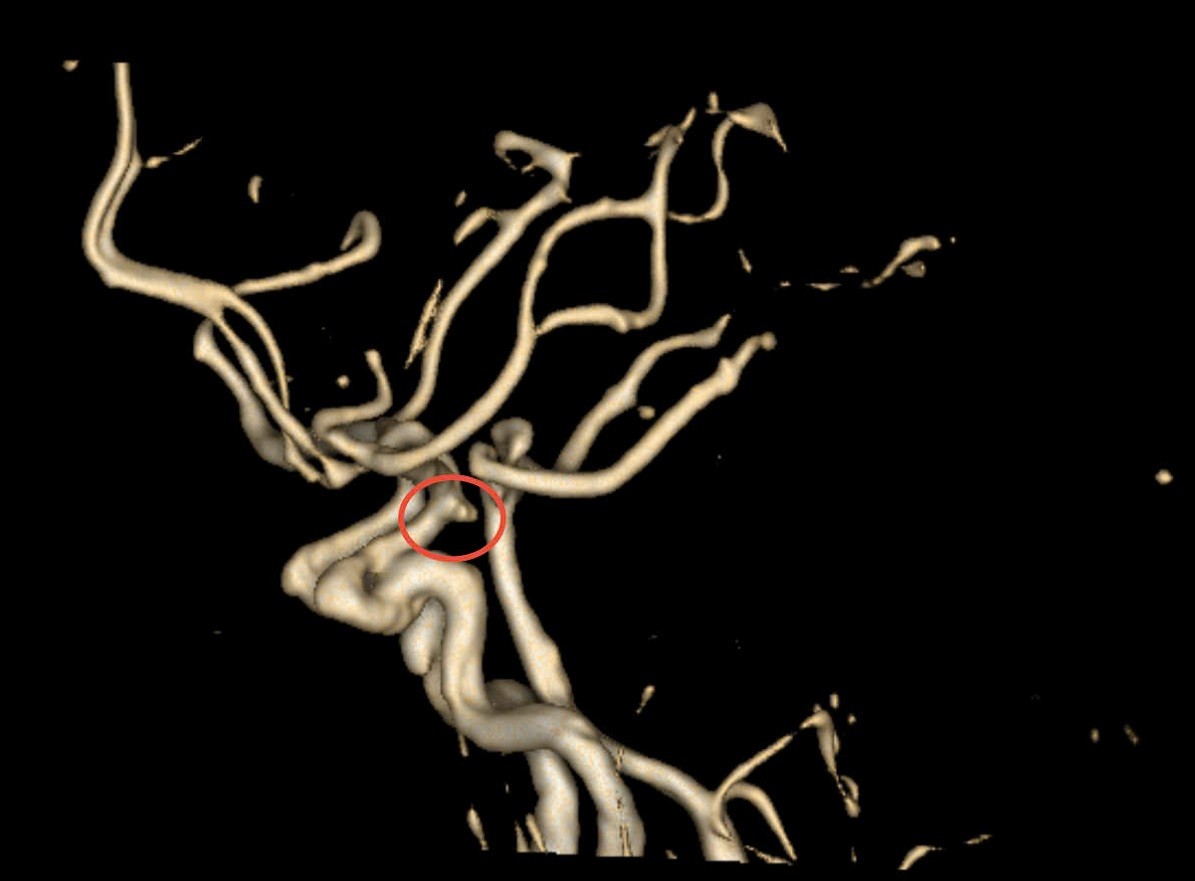

Vị trí túi phình trên phim CTA (Ảnh: BV)

Sau chẩn đoán, bệnh nhân được chụp CT mạch máu não (CTA) và phát hiện túi phình kích thước 7–8 mm ở động mạch cảnh trong đoạn thông sau, vị trí khó quan sát, gần sàn sọ và có dấu hiệu vỡ. Các bác sĩ nhanh chóng hội chẩn đa chuyên khoa và quyết định phẫu thuật khẩn cấp để xử lý túi phình.